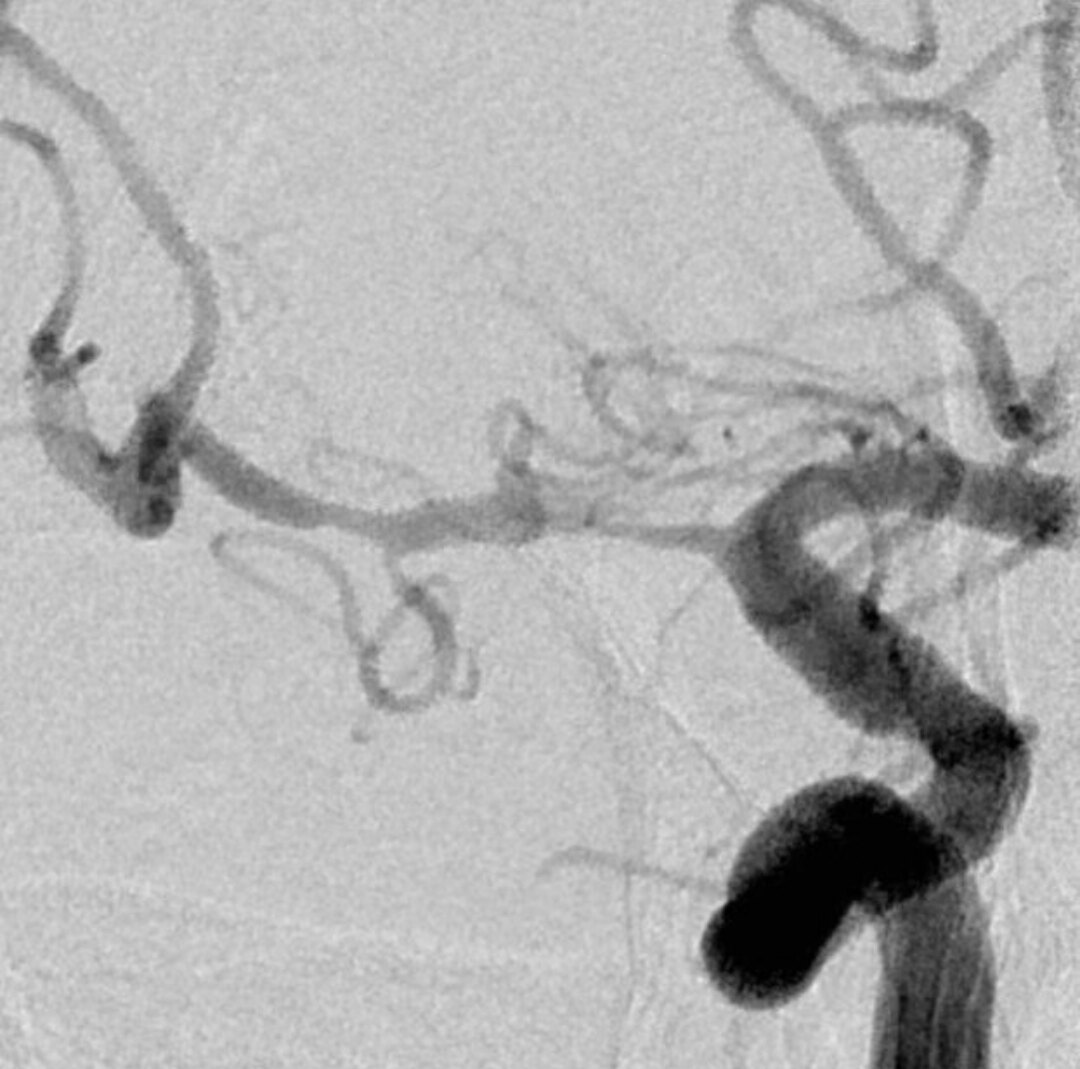

乍一看血管似乎还可以

放大后仔细观看,近端有局限性血管变细,并见双腔征

另外时相远端也隐约局限性变细

半小时后发现近端出现夹层,决定支架植入

确认为夹层,直接支架植入

远端似乎打开不好,由于确认了为夹层,后面支架会进一步打开,无需过多操作,进一步球扩可能会导致高灌注,因为MCA远端的上干已经闭塞,只有下干,手术保留豆纹动脉的通畅为重点

支架进一步打开,直径改善到2.9mm

进一步打开的支架的形态,打开满意